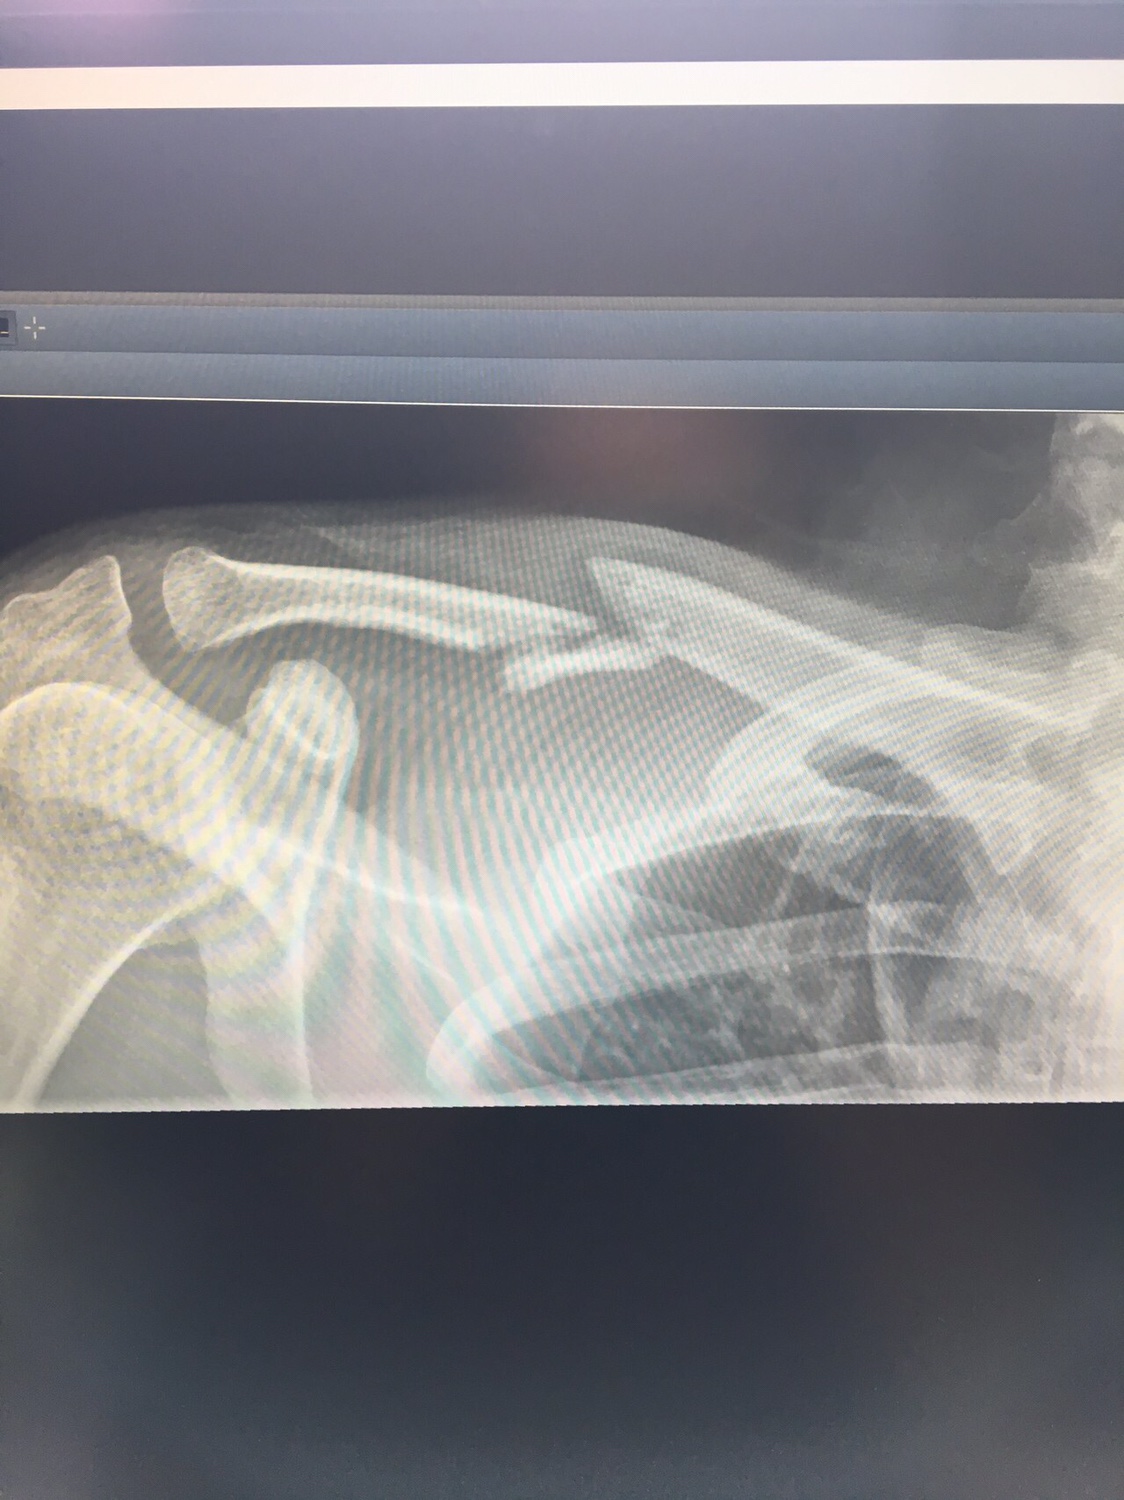

Udo-MH hat geschrieben:Also ich kann ja mal meine 2 cent beisteuern. Auch wenn es nicht das gleiche ist. Ich hatte einen Clavicula RE Trümmerbruch. Die Erste OP war gelaufen und mir wurde eine viel zu dünne Titanplatte eingeschraubt. Die Trümmer von der Assiärztin mit Nähfaden umwickelt. Wenn gewünscht hau ich auch Röntgenfotos rein, was aber für mich zweitrangig ist.

Ok. Erste Platte nach 3 Montaen und der Entfernung des Gilchristverbandes gebrochen. 2. OP. Dickere Platte und Knochenchips aus dem Beckenkamm zu einen Ei geformt um den Bruch. Weil der erste Versuch gescheitert war wurde "nachgefragt". Ich nehme alle 2-3 Tage Diclofenac wegen meines Bandscheibenvorfalls. Das hätte ich lt. Chefarzt NICHT nehmen dürfen. Es verhindert Callusbildung (Knochenverheilung). Dieser Heilprozess ist einer Entzündung gleichzusetzen. Da ich nun Entzündungshemmer nahm war das Ergebnis gleich null.